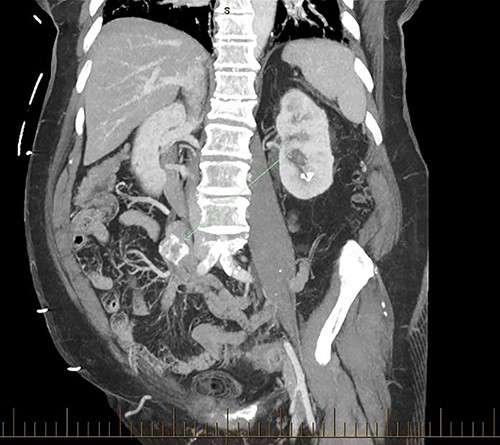

Patient SC is a 72-year-old lady who presented with urosepsis secondary to a left-sided distal ureteric renal stone. Her medical history includes ischemic heart disease, chronic pulmonary obstructive airway disease, type 2 diabetes mellitus, Parkinson’s disease and a previous open cholecystectomy. She was admitted to the intensive care unit and a left-sided nephrostomy tube was inserted. Initial CT imaging incidentally identified a ‘bread clip’-shaped FB in the distal jejeunum (Figs 1 and 2). There was no evidence of obstruction nor perforation. Abdominal X-rays failed to show the presence of a FB.

The acute surgical unit team consulted the patient and initial conservative management included keeping a stool diary and trialling 1 L of glycoprep. Unfortunately, serial imaging failed to show any meaningful progression of the FB. After a successful antegrade ureteric stent insertion, the patient recovered from urosepsis and a decision was made to proceed with a laparoscopic small bowel resection to retrieve the FB.

Intraoperatively, an inflamed segment of 5 cm of the mid jejunum was identified, the FB was palpable and appeared to be partially eroding through the serosa. A SB resection was performed with primary stapled anastomosis. The FB was identified as a BC.

Secondly, as shown in the three cases, unless the BC is calcified, abdominal plain films are not a reliable method of tracking nor diagnosing BC ingestion [9–13]. CT is more sensitive, with a sensitivity rate of 67%, but is not consistently reliable on its own [6, 7]. Reconstructed 3D imaging is effective in identifying BCs. Most BCs are made of low-density polystyrene, a type of versatile solid plastic, which are not readily identified on plain film imaging [14, 15]. This non-degradable plastic means that it is usually only a matter of time before a patient develops a complication.